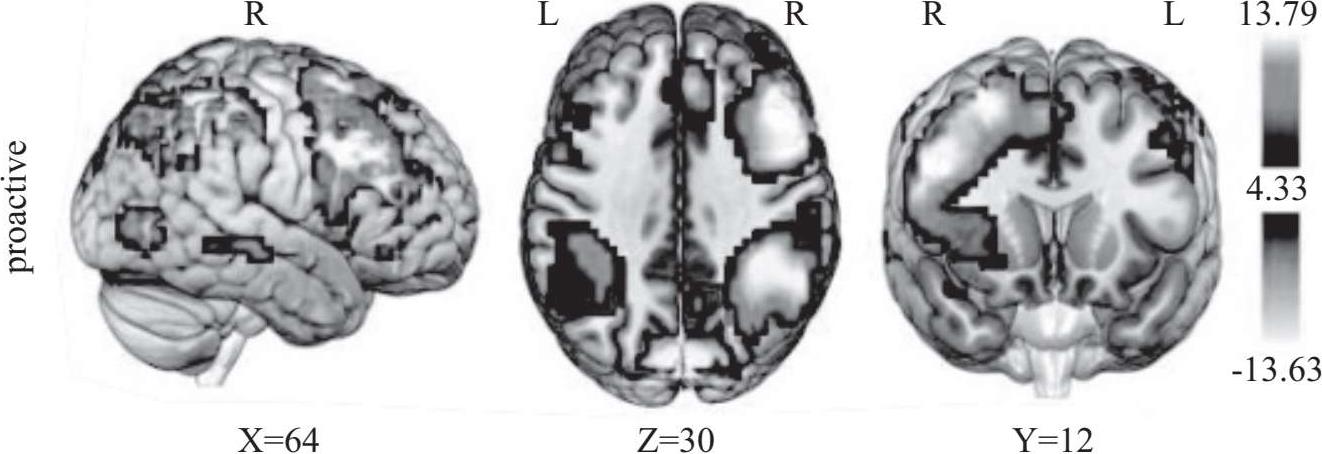

为了更深入地探索这一现象,研究人员运用功能性磁共振成像(MRI)技术对 19 名成年人(25 至 30 岁)和 22 名青少年(13 至 17 岁)的大脑进行扫描。在参与赌博游戏的过程中,研究发现青少年的腹侧纹状体激活程度更高,这一现象即使在两组实验对象面临相同赌注的情况下也依然存在。这表明青少年在追求奖励时更倾向于冒险,以获得更大的回报。这些研究结果表明,青少年大脑对奖励的反应与他们所做出的选择,包括冒险和寻求快乐的行为,直接相关。因此,一些研究人员认为,青少年的这些危险行为可能是由于他们正在发育的大脑中的边缘多巴胺系统过度活跃所驱动的。这解释了为什么青少年更可能尝试诸如酗酒、赌博等高风险行为。

奖励处理过程的研究揭示了奖励预期阶段与体验阶段在神经基础上的分离活动。腹侧纹状体、杏仁核、眶额叶等脑区,以及它们之间形成的神经回路在此过程中发挥着至关重要的作用。对青少年奖励处理过程的脑成像研究指出,青春期的一系列风险行为与大脑区域的发育成熟密切相关。具体来说,负责奖励刺激处理的中脑边缘系统的发育与认知控制的前额叶回路脑区的发展之间存在不平衡的关系。这种不平衡导致了青少年独有的行为特点,包括对奖励的过度反应和冲动控制的不足。这些发现为人们提供了宝贵的视角,以理解和引导青少年在面对各种挑战时的行为选择。通过深入了解青少年大脑的这些特性,人们可以更有效地支持他们的健康成长,帮助他们在关键的青春期做出更明智的决策。

近年来的脑成像研究揭开了奖励处理过程中的一个谜:在奖励预期阶段与结果阶段,大脑神经活动呈现出神经解剖回路的明显分离。特别是在青少年时期,这一时期的主要特征之一是风险寻求行为的显著增加,这表现在奖励相关区域的大脑活动更为频繁,而在规避风险的相关脑区则呈现出较少的神经活动。下面将详细探讨青少年在奖励处理过程中所涉及的主要脑区,包括奖励刺激处理的脑区以及监察风险的脑区,以及这些区域在奖励处理的预期与结果阶段的认知机制和神经活动的变化。通过这一深入分析,人们不仅能够更好地理解青少年的行为和决策模式,而且能够为青少年的心理发展和行为引导提供科学依据。这些脑成像研究的成果不仅对神经科学领域具有重要的科学意义,而且为家长、教育工作者以及心理健康专业人员提供了关于青少年行为背后的生物学基础的宝贵洞见。了解青少年大脑在面对奖励和风险时的反应方式,是帮助他们健康成长和避免潜在风险的关键。